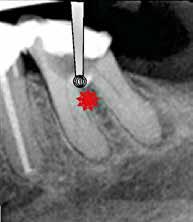

Fig. 2. Tidligere behandlet tand med insufficient eller helt manglende rodfyldning i kanalerne. A. Præmolarer i overkæben med tre insufficiente rodfyldninger og efterfølgende restaurering med stiftopbygning og krone. Desuden første molar uden synlig rodfyldning, men med restaurering, der inddrager pulpakammeret. B. Første molar i overkæben, som kun har synlig rodfyldning i den palatinale kanal. C. Insufficient rodfyldning eller overset rodkanal i første molar i overkæben.

Fig. 2. Previously treated tooth with no or inadequate root filling in canals. A. Maxillary premolars with 3 roots inadequately filled and restored with post and crown. Maxillary first molar with no visible root filling with restoration in pulp chamber and coronal restoration. B. Maxillary first molar with visible root filling only in the palatal canal. C. Inadequate root filling or missed root canal in maxillary first molar.

peroperative faktorer. En af dem er manglende behandling af en rodkanal, enten fordi den ikke blev fundet, eller fordi tandlægen ikke ledte efter den (Fig. 2A-C) (8,9). Det er påvist, at apikal parodontitis forekommer hyppigere i tænder med mindst én ubehandlet eller overset rodkanal (10). Accidentelle perforationer fører ofte til ekstraktion af tanden, men kan almindeligvis undgås med fornuftige endodontiske arbejdsgange (11). Ufuldstændig instrumentering eller forsegling af rodkanalen enten som følge af forkert rodmål eller på grund af fx instrumentfraktur, hyldedannelse eller overinstrumentering af den apikale konstriktion kan føre til, at infektionen persisterer. Rodfile kan frakturere som følge af cyklisk træthedsbrud eller vridningsbelastningsbrud, og incidensraten for brud ligger på 1 % (12). Det sted i tandsættet, der oftest giver anledning til instrumentfraktur, er den apikale del af en mesiofacial rodkanal i en molar (Fig. 3). Kraftig afbøjning af kanalen forøger risikoen for, at filen frakturerer (13). En for kort rodfyldning (> 2 mm fra radiologisk apex) har ligesom overfyldning med guttaperka en nedsat succesrate (14).